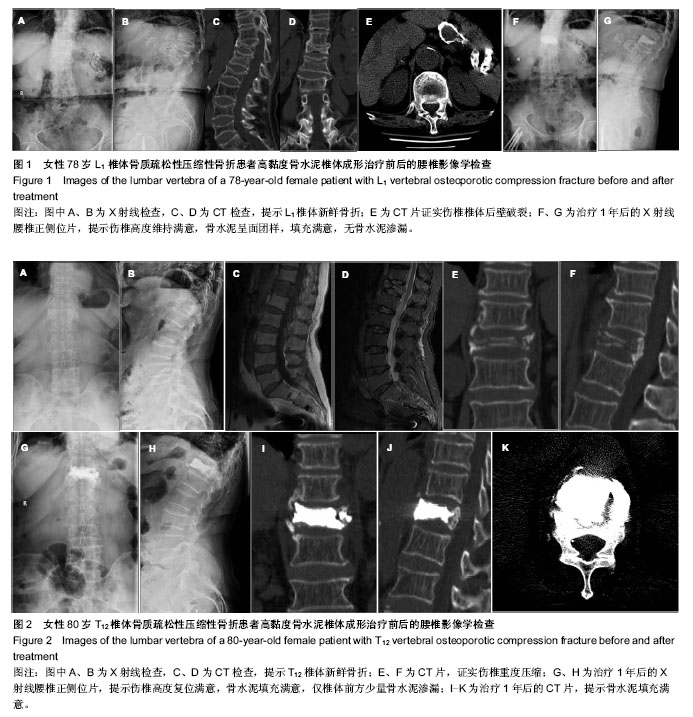

2.1 参与者数量分析 20例患者均顺利完成手术,完成1年以上随访,按意向性处理分析,20例均进入结果分析。 2.2 伤椎椎体前缘高度恢复 治疗后患者伤椎椎体前缘高度得到明显改善,由治疗前的(53.6±10.5)%到治疗后 3 d的(10.3±4.2)%和治疗后1年的(11.5±3.7)%,治疗前后椎体高度比较差异有显著性意义(P < 0.05),治疗后3 d和治疗后1年椎体高度比较差异无显著性意义(P > 0.05),见表1。 2.3 腰背部疼痛及功能恢复情况 术后腰背部疼痛明显缓解或消失,腰背部功能明显改善,生活质量评分得到明显提高,治疗后3 d及1年的目测类比评分、ODI评分明显低于治疗前(P < 0.05),治疗后3 d和治疗后1年的目测类比评分、ODI评分比较差异无显著性意义(P > 0.05)。治疗后3 d及1年的SF-36物理评分及心理评分均高于术前(P < 0.05),治疗后3 d和治疗后1年的SF-36物理评分及心理评分比较差异无显著性意义(P > 0.05),见表1。治疗后神经功能均正常为Frankle E级,与治疗前相同。 2.4 并发症及不良反应 所有手术均顺利完成,每个椎体注射骨水泥量2-5 mL,术中血压及血氧饱和度均正常。治疗后随访12-18个月,平均14.5个月。术后复查X射线及CT见骨水泥弥散良好,只有1例发生椎管内少量骨水泥渗漏及1例椎体前方渗漏,但无任何临床症状,无骨水泥毒性或过敏反应、肺栓塞、感染和神经损伤等并发症发生。随访期间无新发骨折。"